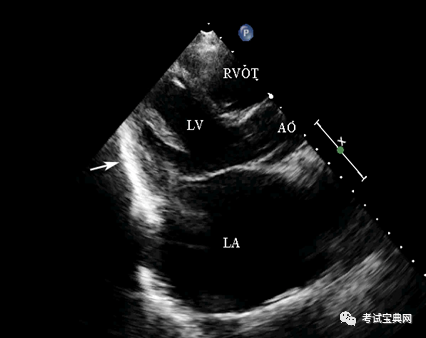

3.超声心动图:临床最常用的无创检测手段

典型表现为心包增厚、黏连心脏变形 , 室壁活动减弱 , 室间隔舒张期矛盾运动 , 即室间隔

抖动征) , 下腔静脉增宽且不随呼吸变化

文章插图

缩窄性心包炎心包明显增厚